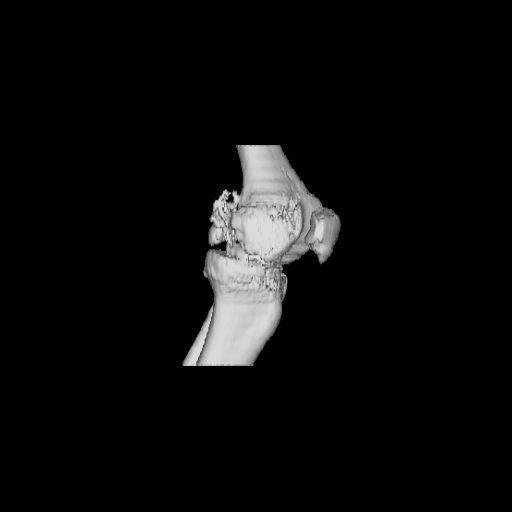

Before the CT and MRI era, we were treating the fractures with study of the Xrays alone. Such fractures with skeletal traction followed by non wtbearing mobilisation used to yield a fairly good range of movements. The CT gives a real ghastly picture of not so bad looking plain Xrays. I think this case needs traction to start with to correct the flexion deformity which probably will be achieved in 2 weeks time or less. We can then reassess the case with fresh Xrays. If possible one should try and fix the fragments to get some alignment. But the fixation should be stable enough to be able to mobilise the joint. Otherwise the traction can be continued for another 2 weeks to make the fracture sticky and then mobilise. We could get about 70 to 80* movements in spite of such communition. I am enclosing an Xray of a patient who is walking independantly and has 0 to 80* movemnts of the knee for the last one year

This is a coronal split in the femoral condyle and is a rare injury. Please see attachment for ORIF result

|